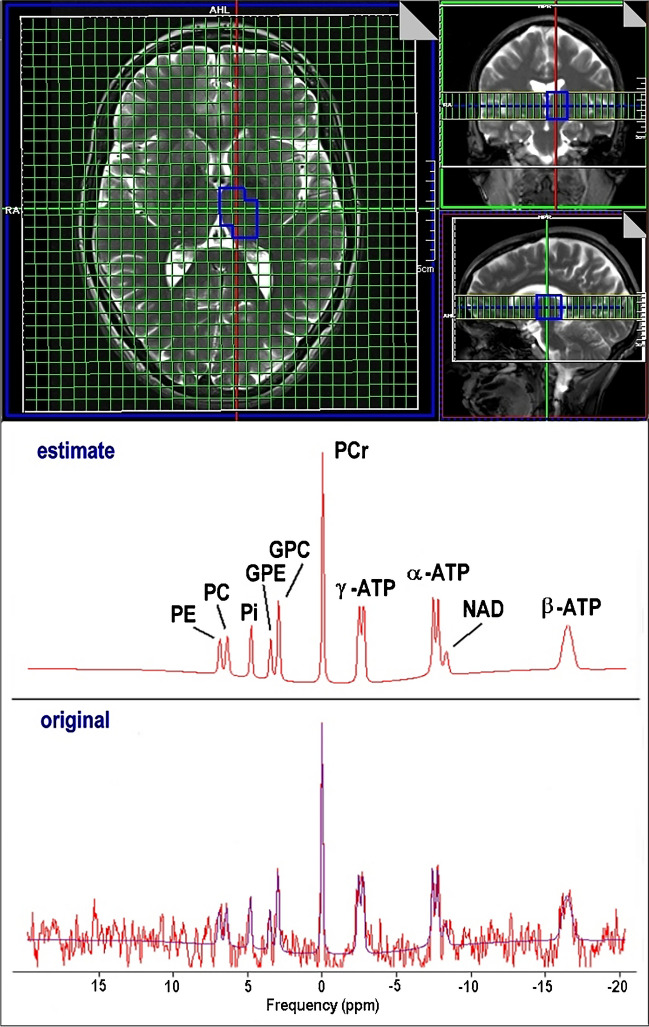

Phosphorus CSI data were transferred to a Leonardo workstation (Siemens Healthcare GmbH, Erlangen, Germany) and interpolated to a 32 × 32 × 8 grid resulting in a stack of 8 axial slices with 25 mm thickness (voxel size 6.3 × 6.3 × 25 mm3 ≈ 1 ml) which were superimposed on axial T2-weighted slices (Fig. 1). Anatomical volumes of interest (VOI) for spectral evaluation were identified by manually (M.F., M.B., and S.B.) selecting appropriate voxels in the grid. Grid shift in-plane as well as in head-feet direction was applied to optimally enclose the respective anatomical region of interest. Nine different VOIs were delineated for each subject in FGM, l_FWM, r_FWM, l_TH, r_TH, l_BG, r_BG, l_TL, and r_TL. VOI size ranged from 7 to 18 ml.

Quantitative analysis of the 31P spectra was performed with the jMRUI software tool (version 5.1) employing the AMARES algorithm [ref. 48]. The model function was composed of 14 resonances including PE, PC, Pi, GPE, GPC, PCr, ATP, and one macromolecular component to account for the broad signal baseline (Fig. 1). ATP was represented by a total of 7 peaks: a doublet γ-ATP, a doublet α-ATP, and a triplet β-ATP. Constraints for frequency, damping, coupling constants, and amplitude ratios (prior knowledge) were defined for the compounds to be estimated by the algorithm. The resulting amplitude values are proportional to the corresponding metabolite concentration. The concentration of ATP was calculated from the γ-ATP resonance. Only spectra with SNR higher than 3 were included for further analysis.